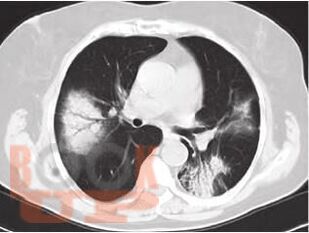

В настоящем учебном пособии освещены принципы ведения пациентов диссеминированными заболеваниями легких. Обсуждаются вопросы этиологии, патогенеза, диагностики, а также основные методы лечения пациентов с фиброзирующими альвеолитами. Учебное пособие предназначено для врачей общей практики, участковых терапевтов, аллергологов, пульмонологов.